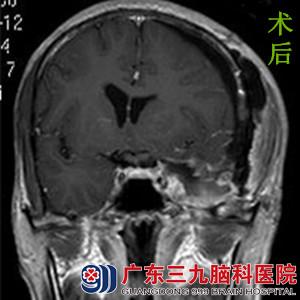

在朋友的帮助下,曾先生来到广东三九脑科医院综合神经外科鲁明主任处就诊,行头颅MR检查提示左侧鞍旁海绵窦、蝶骨嵴内侧巨大占位,大小约4.56cm*4.32cm*5.54cm。病变血供较丰富,左侧颈内动脉海绵窦段、左侧大脑中动脉受压上抬移位,与其关系密切。完善相关检查后,由鲁明主任主刀,在全麻下行左侧鞍旁海绵窦、蝶骨嵴内侧巨大脑膜瘤切除术,术中显微镜下见灰白色肿瘤位于左侧鞍旁蝶骨嵴区,向海绵窦内生长,质软,血供一般,边界清楚,予肿瘤切除,手术顺利结束。术后经治疗,患者康复出院。术后病理结果:过渡型脑膜瘤。